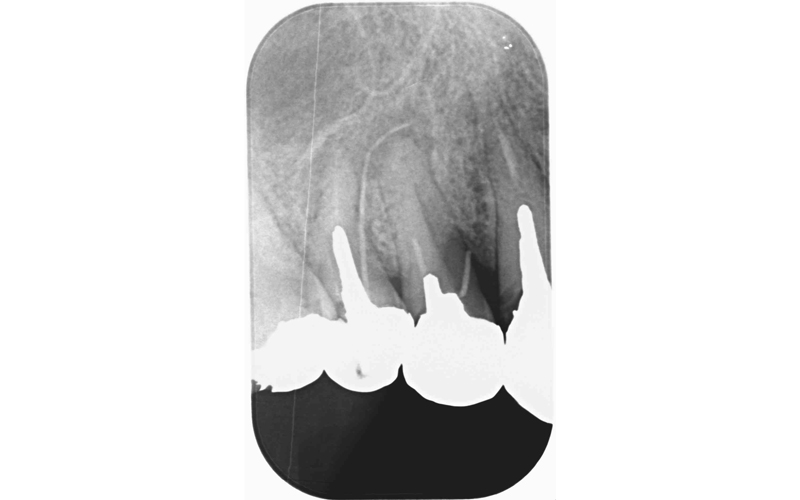

| 備考 | 噛む力が強く、上の前歯裏の金属により下の前歯が神経に達するぐらい擦れている状態だった。 それと共に右上下のむし歯により抜歯が必要であり、入れ歯では今後の維持が難しくインプラントにより噛み合わせを確立する治療選択となった。 |